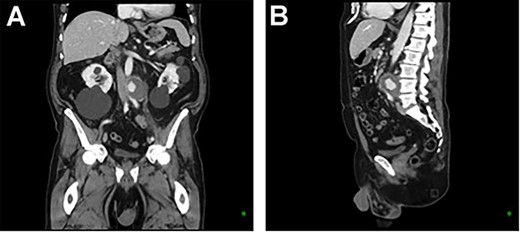

A 73-year-old male presented with a 1-week history of back pain on a background of hypertension, atrial fibrillation and bladder cancer. Computed tomography (CT) angiography demonstrated a 47 × 46 × 47 mm saccular aortic pseudoaneurysm of the infrarenal aorta with a contained rupture (Fig. 1). The patient remained hemodynamically stable with mildly elevated inflammatory markers (C-Reactive Protein (CRP), 85 mg/l, white cell count (WCC) 6.5 × 109/l). The abdominal aorta 5 months previously was normal on CT when a course of intra-vesical BCG for transitional cell carcinoma of the bladder had been ceased due to the development of fevers and syncope. Thus, Mycobacterium bovis involvement of the false aneurysm was suspected. Emergent endovascular repair was performed with a covered stent graft system successfully excluding the ruptured aneurysm sac on post-operative CT angiogram. A CT-guided fine needle aspirate of the aneurysmal sac was later conducted (Fig. 2). PCR of the aspirate returned a low-positive result confirming the diagnosis with M. bovis subsequently isolated on culture. Empirical antibiotics were ceased and he was commenced on a planned 18-month antituberculosis regimen of ethambutol, isoniazid and rifampicin guided by gene deletion analysis (GeneXpert MTB/RIF Ultra assay). Fluorodeoxyglucose-positron emission tomography (FDG-PET) scan was used to monitor the level of activity of the infection (Fig. 3). The patient was discharged home on Day 10 of admission. Aneurysm sac size was decreased at 3 and 6 months on CT angiogram and FDG-PET but there was ongoing FDG avidity around the aneurysm sac; there were no other sites of involvement. The patient remains otherwise well and has returned to his premorbid activities.

CT aortic angiography demonstrating a 47 × 46 × 47 mm infrarenal aortic pseudoaneurysm with an area of contrast filling and associated mass displacement of the aorta and inferior vena cava. (A) Coronal and (B) sagittal.